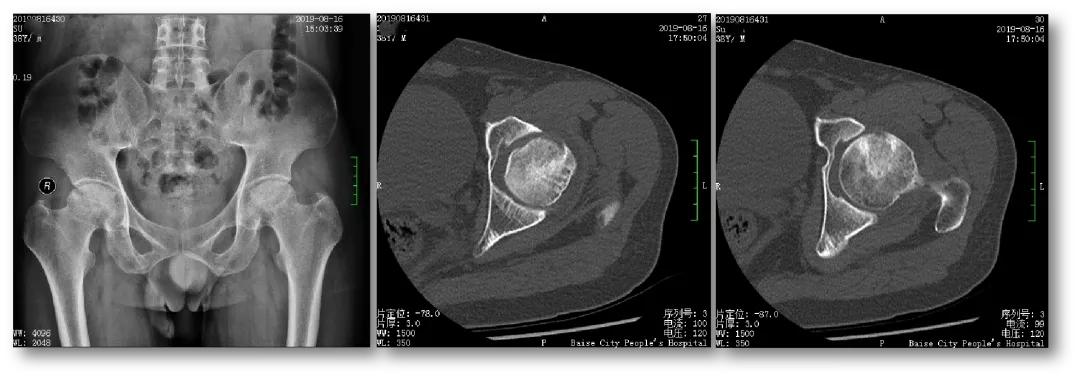

案例一

云南的苏先生今年38岁,出现双侧髋关节疼痛、活动受限1年多,被 明确 诊断为“双侧股骨头坏死”,坏死处于ARCO分期3期。在当地医院使用多种办法治疗,无明显效果,而后转到百色市人民医院关节与运动医学科。在患者及其家属强烈的保髋愿望下,科室选择了骨科机器人辅助下的微创保髋治疗,术后效果良好,患者满意。

术前辅助检查